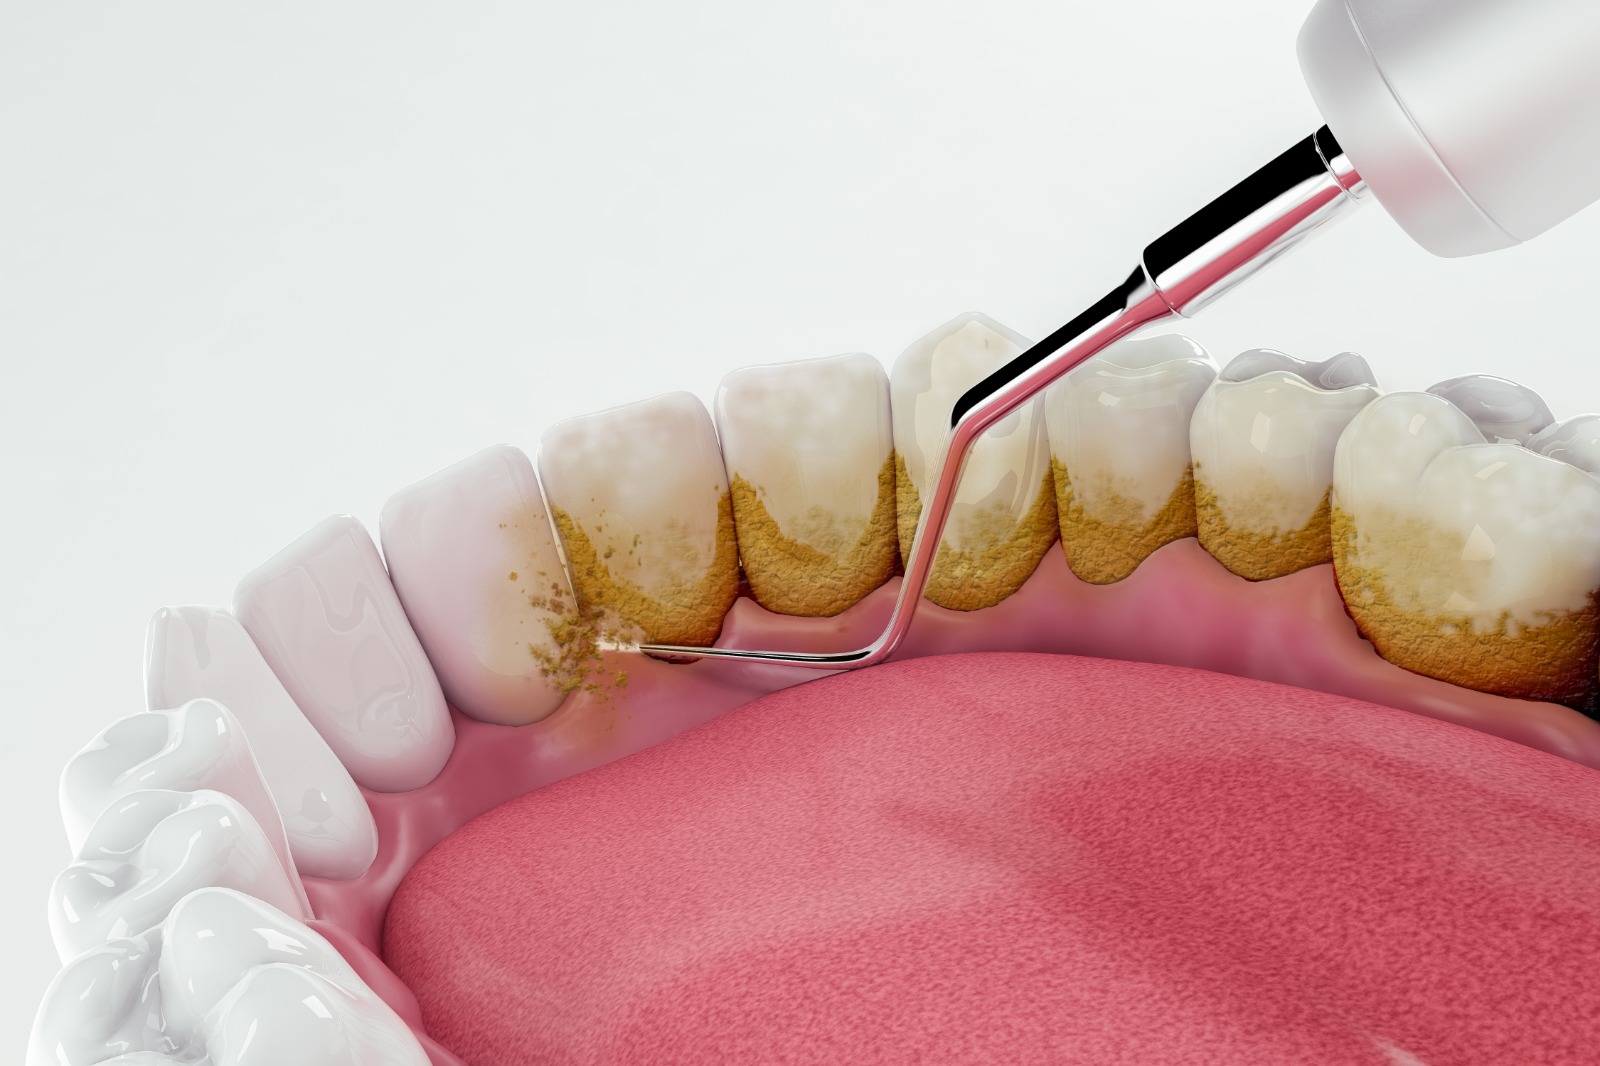

DİŞ TEMİZLEME-DETERTRAJ

Deteraj, diş yüzeyinde sarı veya kahverengi tonlarında oluşan ve belirginleşen diş taşlarının, profesyonel temizlik yöntemiyle temizlenmesi işlemidir.